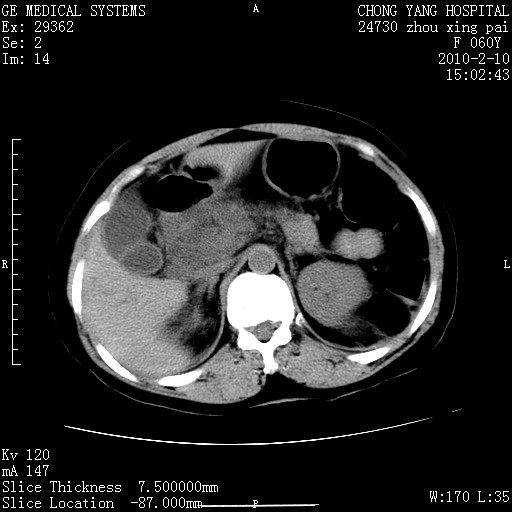

标题: CT24682:F60Y 腹痛 其它不详 [打印本页]

标题: CT24682:F60Y 腹痛 其它不详

胆总管末端梗阻!结石?肿瘤?建议增强!必要时行ercp!

胆总管末端梗阻!结石?胰腺影增粗,以胰腺头部为著,胰周看见渗出影,双侧胸腔积液,(胸膜反应)考虑胰腺炎。

1)胆总管末端梗阻,不排除结石所致可能。2)胰腺炎。3)慢性胆囊炎可能。4)左侧输尿管上段扩张。5)少量腹水。6)双侧少量胸腔积液,伴两下肺部分肺萎陷。

1)胆囊炎。2)胆源性胰腺炎。3)右肾周筋膜增厚,肾旁前间隙积液。4)左侧输尿管上段扩张。5)少量腹水。6)双侧少量胸腔积液,伴两下肺部分肺膨胀不全。

急性胰腺炎所致胆总管扩张!

1)胆总管末端梗阻。2)胰腺炎。3)慢性胆囊炎可能。4)左侧输尿管上段扩张。5)少量腹水。6)双侧少量胸腔积液,伴两下肺部分肺萎陷。